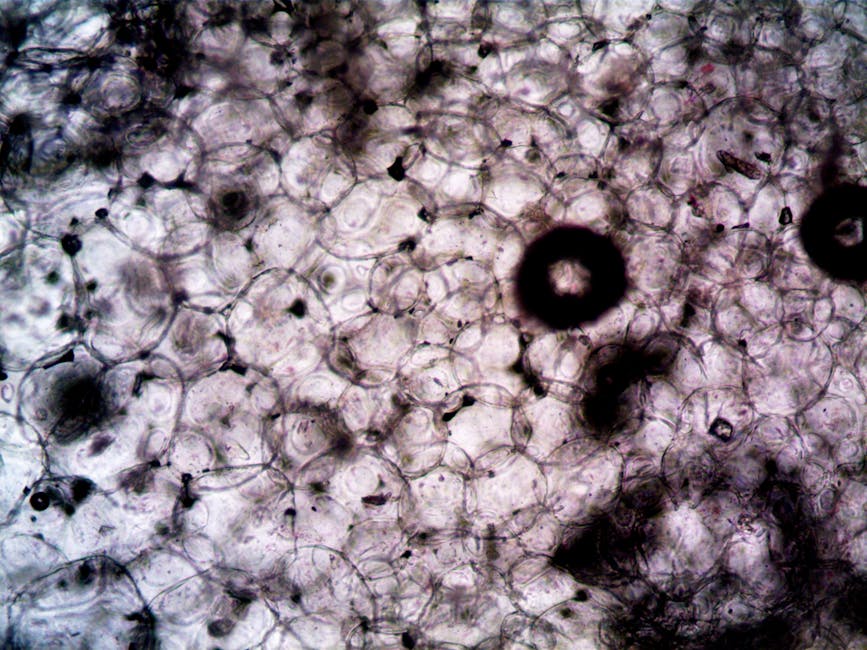

A new study sheds light on the role of “zombie” immune cells in liver disease